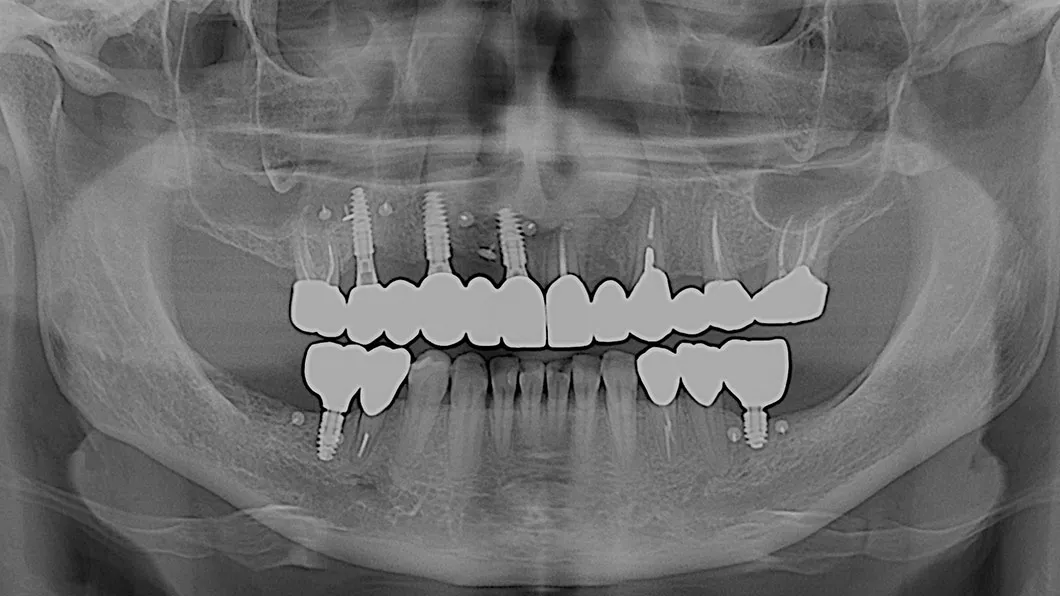

Клинический случай 3 имплантация зубов

Пациентка обратилась с жалобами на неудовлетворительный внешний вид старых коронок и мостовидных протезов, а так же дискомфорт и боль при жевании, в связи со значительной подвижностью конструкций.

Лечение: снятие старых коронок и мостовидных протезов. Удаление зубов, не подлежащих лечению. Костная пластика и десневая пластика. Установка 3-х зубных имплантатов на верхней челюсти и 2-х имплантатов на нижней челюсти.

Протезирование: цельнокерамическими мостовидными протезами и коронками на зубах, имплантатах.